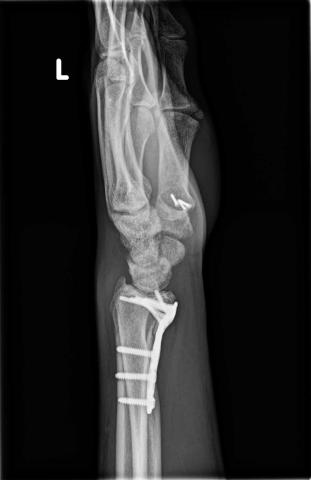

In just the past two years, Georgilopoulos has survived three broken wrists, a torn hamstring, tendonitis in both knees, and a motorcycle accident that left him with 14 screws and a plate in his wrist

His most recent operation — an arthroscopic shoulder stabilisation performed by Dr Andrew McBride, a Bond University Honorary Adjunct Assistant Professor — has left him upbeat about another comeback. He’s now in the thick of rehab with the Bond Physio team and is forecast to return to vaulting in August.